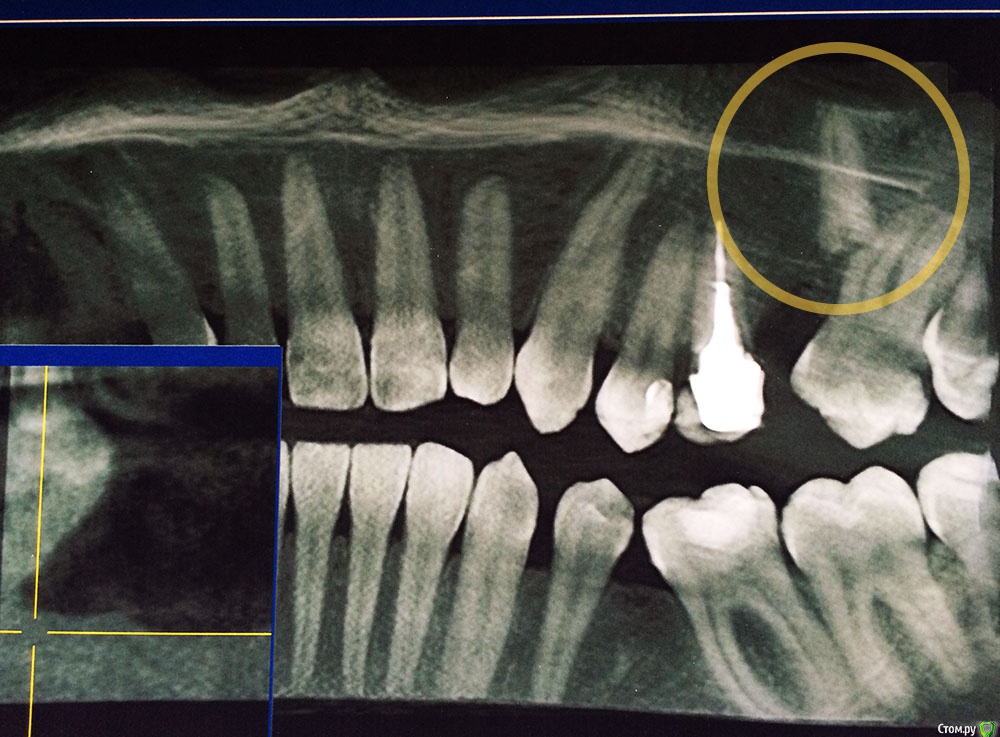

Подскажите, пожалуйста! Удалял зуб 10 лет назад, сейчас обнаружили на снимке, что он удален не полностью — остался кусок корня зуба, который очень глубоко затолкали при удалении, чуть ли не в пазуху носа.

Снимки прилагаю. Направили в ЧЛХ на операцию, собрал все анализы, противопоказаний нет, а ложиться не хочется, как обычно   :ph34r:

Здравствуйте, корень скорее всего не в пазухе, если имеете кт на руках, выставите срезы на корень, квадрат с перекрестьем на корень наведите и выложите срезы сюда, может ЧЛХ и не потребуется.